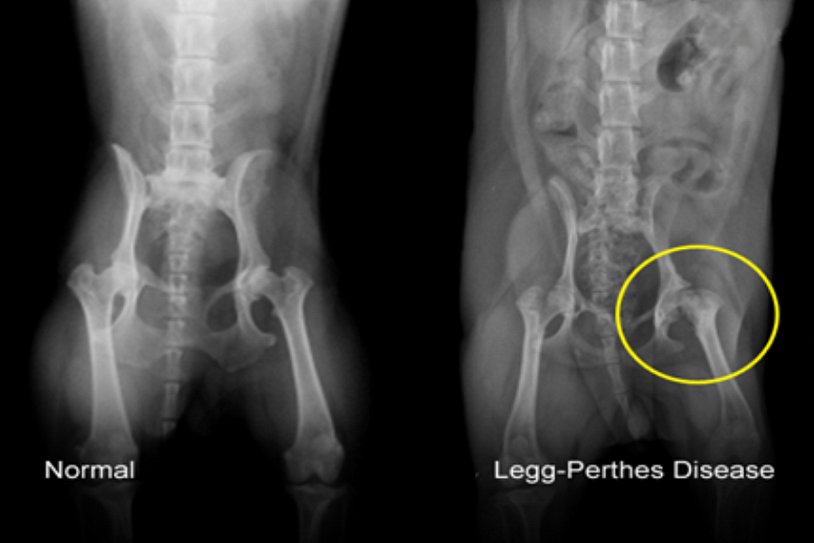

Некроз тазобедренного сустава: Фотографии и особенности лечения